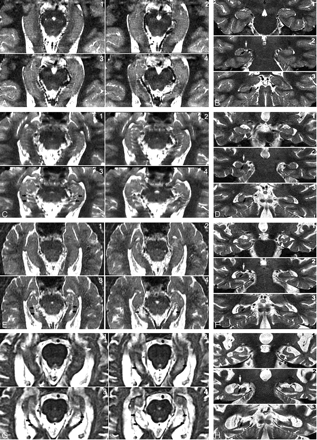

The perihippocampal fissures (PHFs) include the lateral part of the transverse fissure, the choroidal fissure, and the hippocampal fissure.2(Fig 2A, -B) The transverse fissure is the lateral extension of the ambient cistern, which separates the thalamus superiorly from the perihippocampal gyrus inferiorly. The superior lateral extension of the transverse fissure is the choroidal fissure, which extends superior to the hippocampus. The inferior lateral extension of the transverse fissure is the hippocampal fissure, which extends between the cornu ammonis and the subiculum (Fig 2). The uncal sulcus may be noticed in the head of hippocampus (Fig 3G, H). We used a 4-point subjective scale to rate the size of the perihippocampal fissures on the axial T2 images.2 The PHF in all cases were rated independently by 2 radiologists (Y.L. and J.Z.) blinded to patient clinical status. The intraclass correlation coefficient for inter-reader reliability was 0.95. For all cases with disagreements in the ratings, a final consensus diagnosis was achieved. For each hemisphere, PHF was rated on the axial T2 imaging by using the following atrophy scoring: 0, none; 1, questionable; 2, mild/moderate; and 3, severe2 (Fig 3). An individual subject’s total PHF score was determined by summing the scores across hemispheres.

Four-point subjective rating scale of the perihippocampal fissures (PHF).

A and B, Axial and coronal view of same case. Left = 0; right = 0

C and D, Axial and coronal view of same case. Left = 1; right = 1

E and F, Axial and coronal view of same case. Left = 2; right = 2

G and H, Axial and coronal view of same case. Left = 3; right = 3

Axial images were reformatted in 1-mm thickness from inferior to superior, paralleling to the long axial of hippocampus. Black arrows highlight the PHF. There are 3 coronal views for each case showing the head, bodyi and tail of hippocampus. Black arrows highlight the PHF. White arrows on coronal plane show lateral geniculate body. Arrowheads on coronal plane show uncal sulcus.